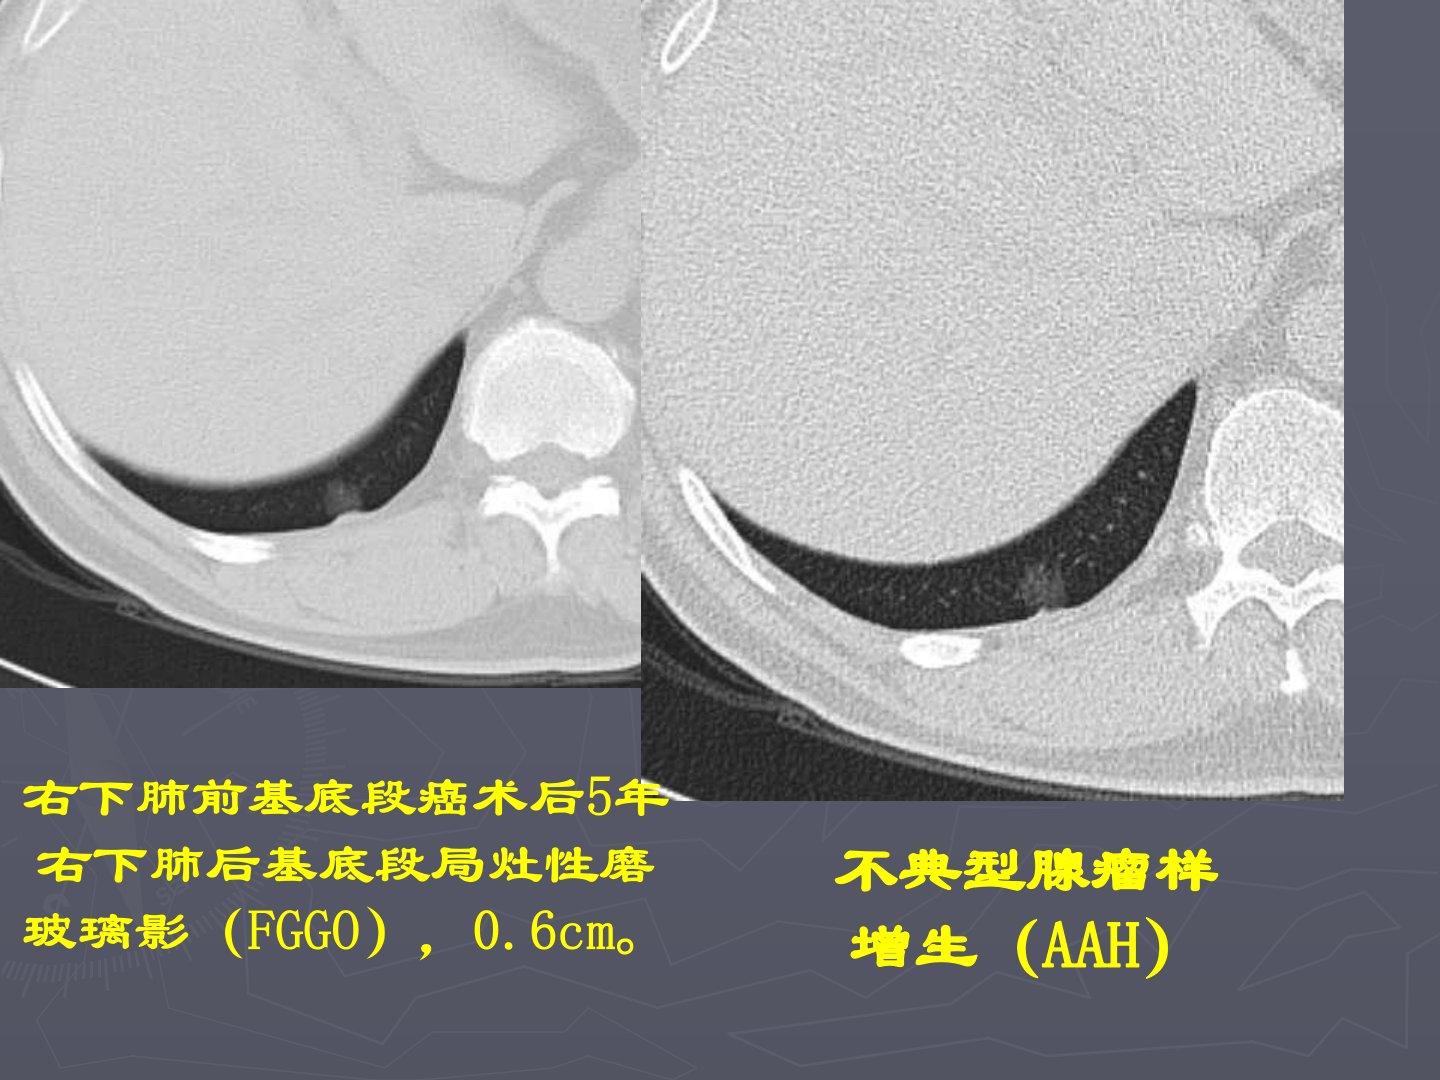

肺部结节的鉴别诊断肺癌的病理分型及亚型鳞状细胞癌:乳头状鳞癌、透明细胞鳞癌、小细胞鳞癌、基底细胞样鳞癌。腺癌:乳头状腺癌、腺泡样腺癌、粘液腺癌、细支气管肺泡癌(粘液型18%、非粘液型82%预后好、混合型)、混合亚型腺癌(最多见,占80%,多伴有BAC)。小细胞肺癌大细胞肺癌不典型腺瘤样增生(AAH)右下肺前基底段癌术后5年右下肺后基底段局灶性磨玻璃影(FGGO),0.6cm。BAC42/F体检发现右肺结节。另一个BAC细支气管肺泡癌(BAC)AAH54/F体检发现右肺结节。AAH68/M,食管癌术前CT发现左上肺边缘较光整、边界清晰的类圆形NGGO,3cm。中分化腺癌与BAC混合亚型54/M体...